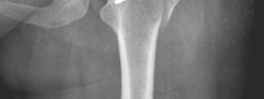

- Femoral Head and Neck: The anatomical relationship between the femoral head and neck is crucial. A CAM lesion manifests as an increased radius of curvature at the anterior-superior femoral head-neck junction, leading to abutment against the acetabular rim, particularly during hip flexion and internal rotation. This contact causes shear forces on the labrum and adjacent articular cartilage.

* CAM Impingement: The aspherical femoral head-neck junction abuts the acetabular rim and labrum during hip flexion and internal rotation, causing a "pistoning" effect that shears the labrum off the cartilage and leads to chondral damage from the periphery inwards. The alpha angle, a radiographic measure, quantifies the femoral head-neck sphericity.

* The prominent aspect of the femoral head-neck junction (CAM lesion) is resected using osteotomes or high-speed burrs. The goal is to restore the normal offset and sphericity of the femoral head, preventing further impingement.

* The resection should be precisely controlled to avoid over-resection, which can lead to femoral neck fracture, or under-resection, which results in residual impingement. The alpha angle is assessed intraoperatively.